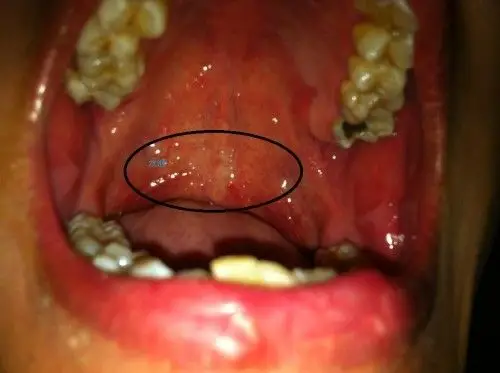

我做过扁桃体手术,我发现我咽道壁上长满水泡一样的东西是什么,会变成

软腭上面有许多小水泡. 咽喉疼痛,去第二医院说没什么问题.

我喉咙里那个水泡是什么情况?淋巴泡增生吗?如何治疗?如何保养?

扁桃体手术后左侧长水泡有脓,不适感

扁桃体大面积起泡,伴随高烧(高达39.